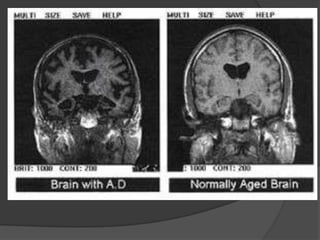

ALZHEIMER’S DEMENTIA

Structural imaging

Cerebral atrophy (typical dilatation of lateral

ventricles & widening of cortical sulci) particularly in posterior temporal & parietal regions &

 specific brain regions like hippocampus and medial

temporal lobe.



Volumetric MRI reveals shrinkage in vulnerable

brain regions, particularly the medial temporal lobe

& Hippocampus.

Measurements of hippocampus is the most sensitive marker of

pathology of AD early in disease